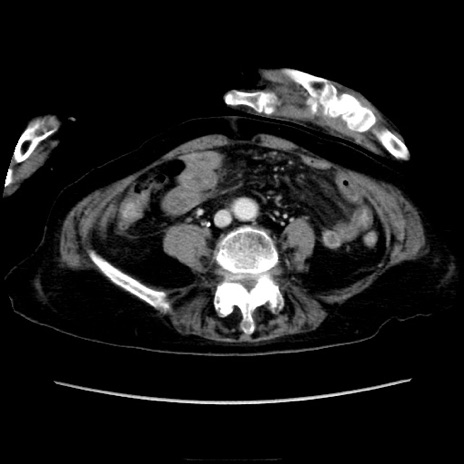

症例40(横断像)

【症例】90歳代女性

【主訴】腹痛・嘔吐

【現病歴】 食欲低下、嘔吐があり昨日他院受診。肺炎と診断され入院となる。入院後より腹部全体に圧痛あり。胃管留置され経過みていたが、症状持続するため、

当院転院となる。

【既往歴】胸椎圧迫骨折、胆石症

【身体所見】腹部:中央に激痛あり、圧痛あり、反跳痛不明

【データ】WBC 17100、CRP 18.82

横断像